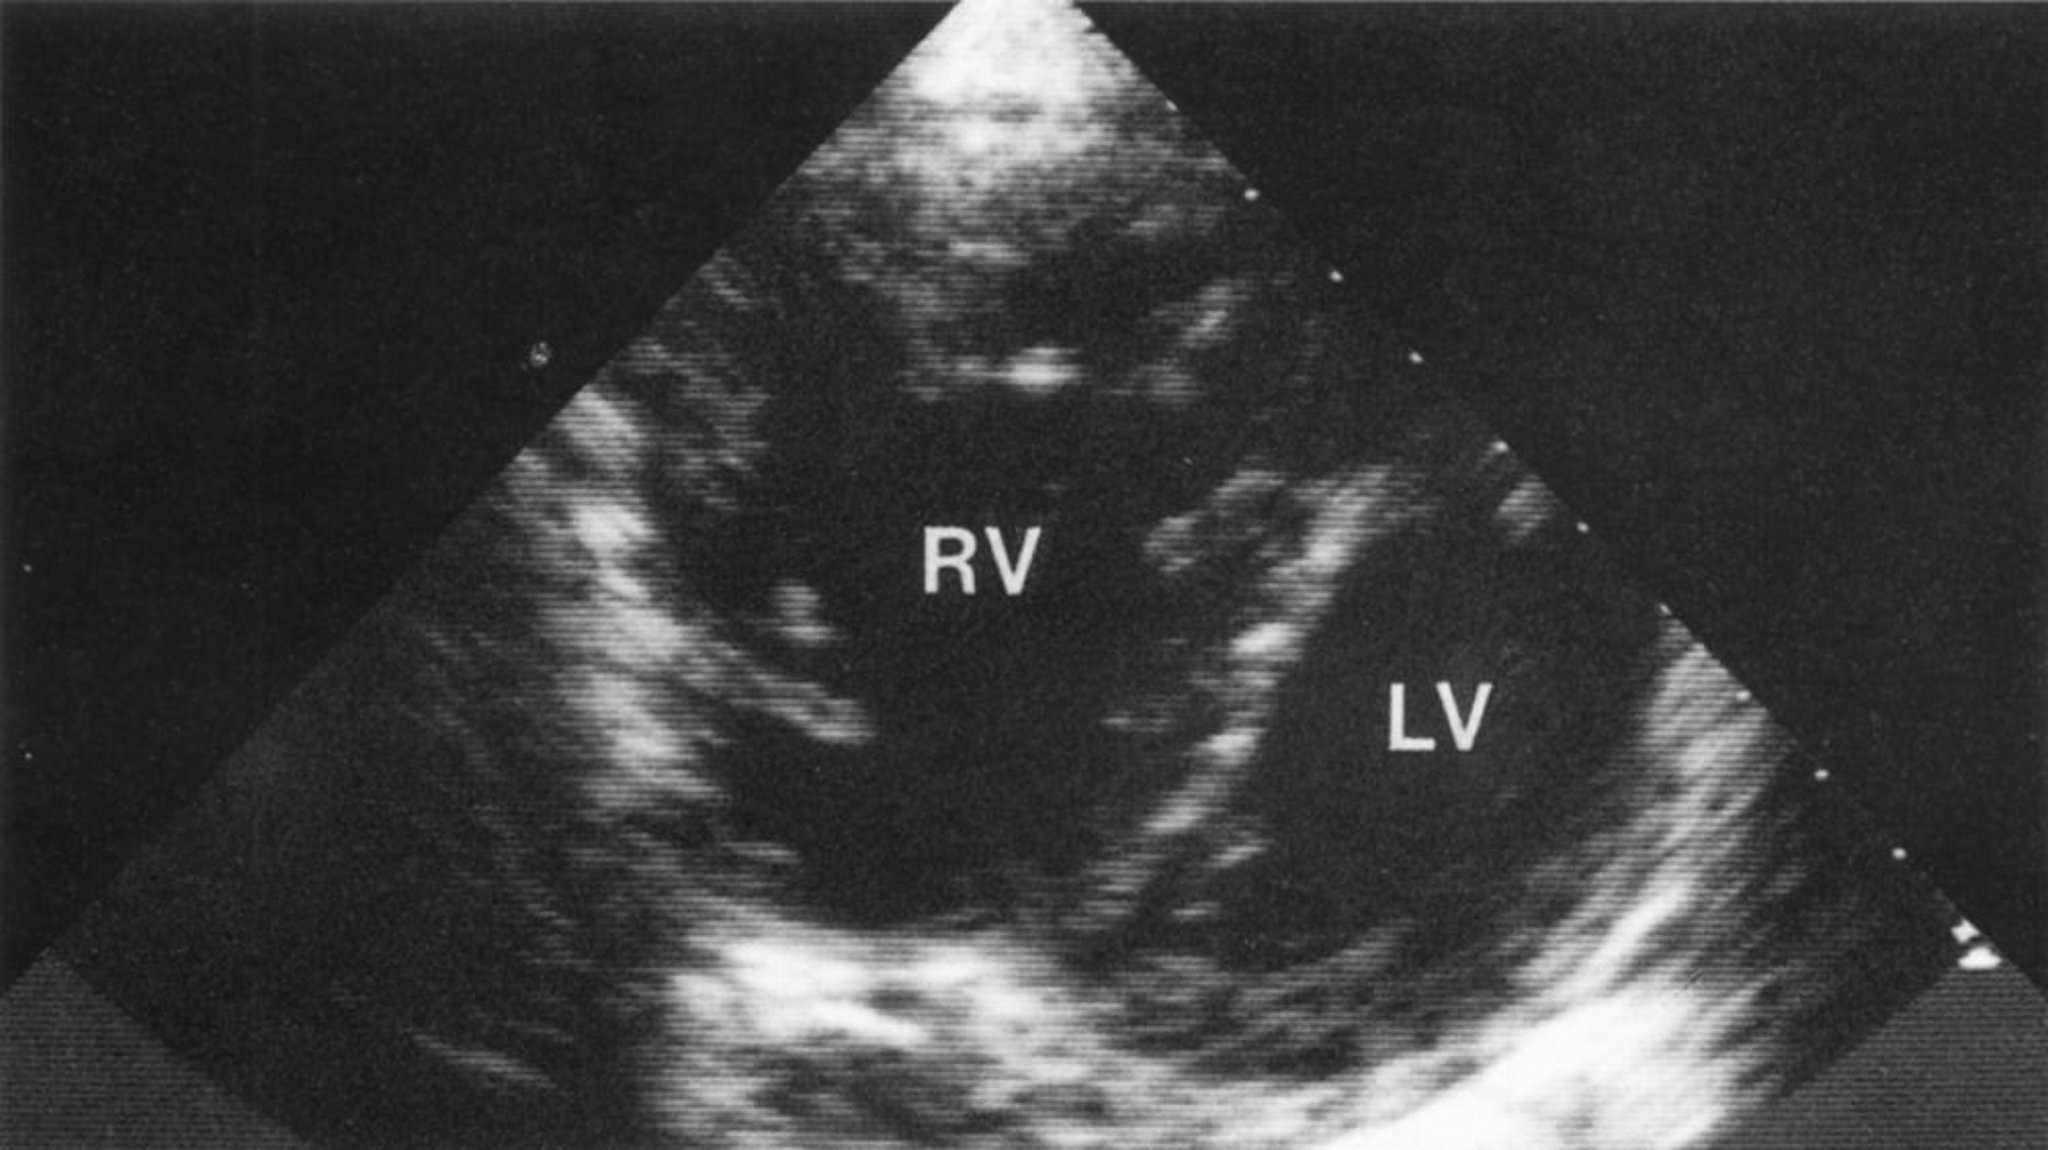

Cardiopatía pulmonar (ecocardiografía)

Vista longitudinal corta que muestra un ventrículo derecho muy aumentado de tamaño con hipertrofia del ventrículo derecho. La inclinación anormal del tabique interventricular hacia el ventrículo izquierdo da una configuración en D característica del ventrículo izquierdo, lo que es compatible con una sobrecarga de volumen y presión en el ventrículo derecho.